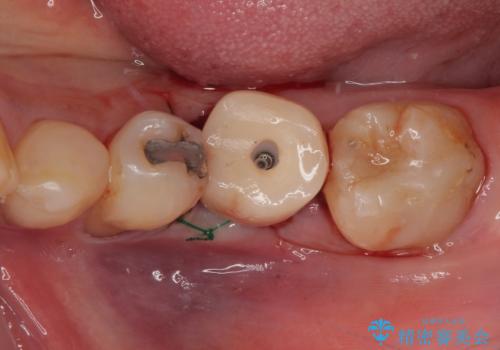

下顎大臼歯の抜歯即時埋入インプラント治療では、複数ある歯根のうち、後方の歯根部にインプラントを埋入することで一般的であり、今回破折して骨吸収が著しいのは前方の歯根であったため、事前に仮歯を用意した上で、抜歯即時埋入インプラントによる補綴治療を行うこととしました。

来院されるまではインプラント治療を躊躇されていましたが、抜歯即時埋入により、単回の外科処置で治療が終えられることのメリットを理解され、インプラントによる補綴治療を行いました。

スムーズに治療を終えることができました。